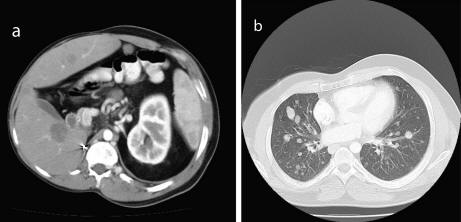

WilmsTumor In A 37-Year-Old - Researchgate.net

Wilms’ Tumor in a 37-Year-Old Abstract Wilms’ tumor is rare in adults. Though the approach to diagnosis to alternative treatment for adults where initial chemothera-py fails or the disease recurs. While the concern in children ... Return Doc